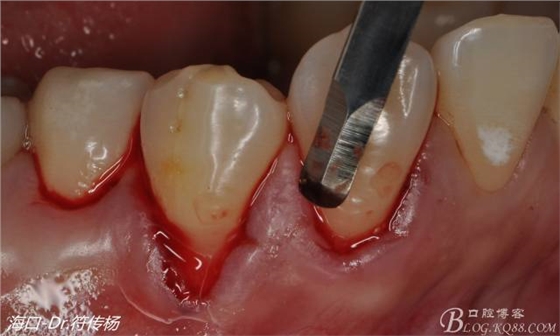

首先用顯微手術(shù)刀切斷手術(shù)范圍內(nèi)的牙周韌帶

然后使用下頜開隧刀剝離牙齦